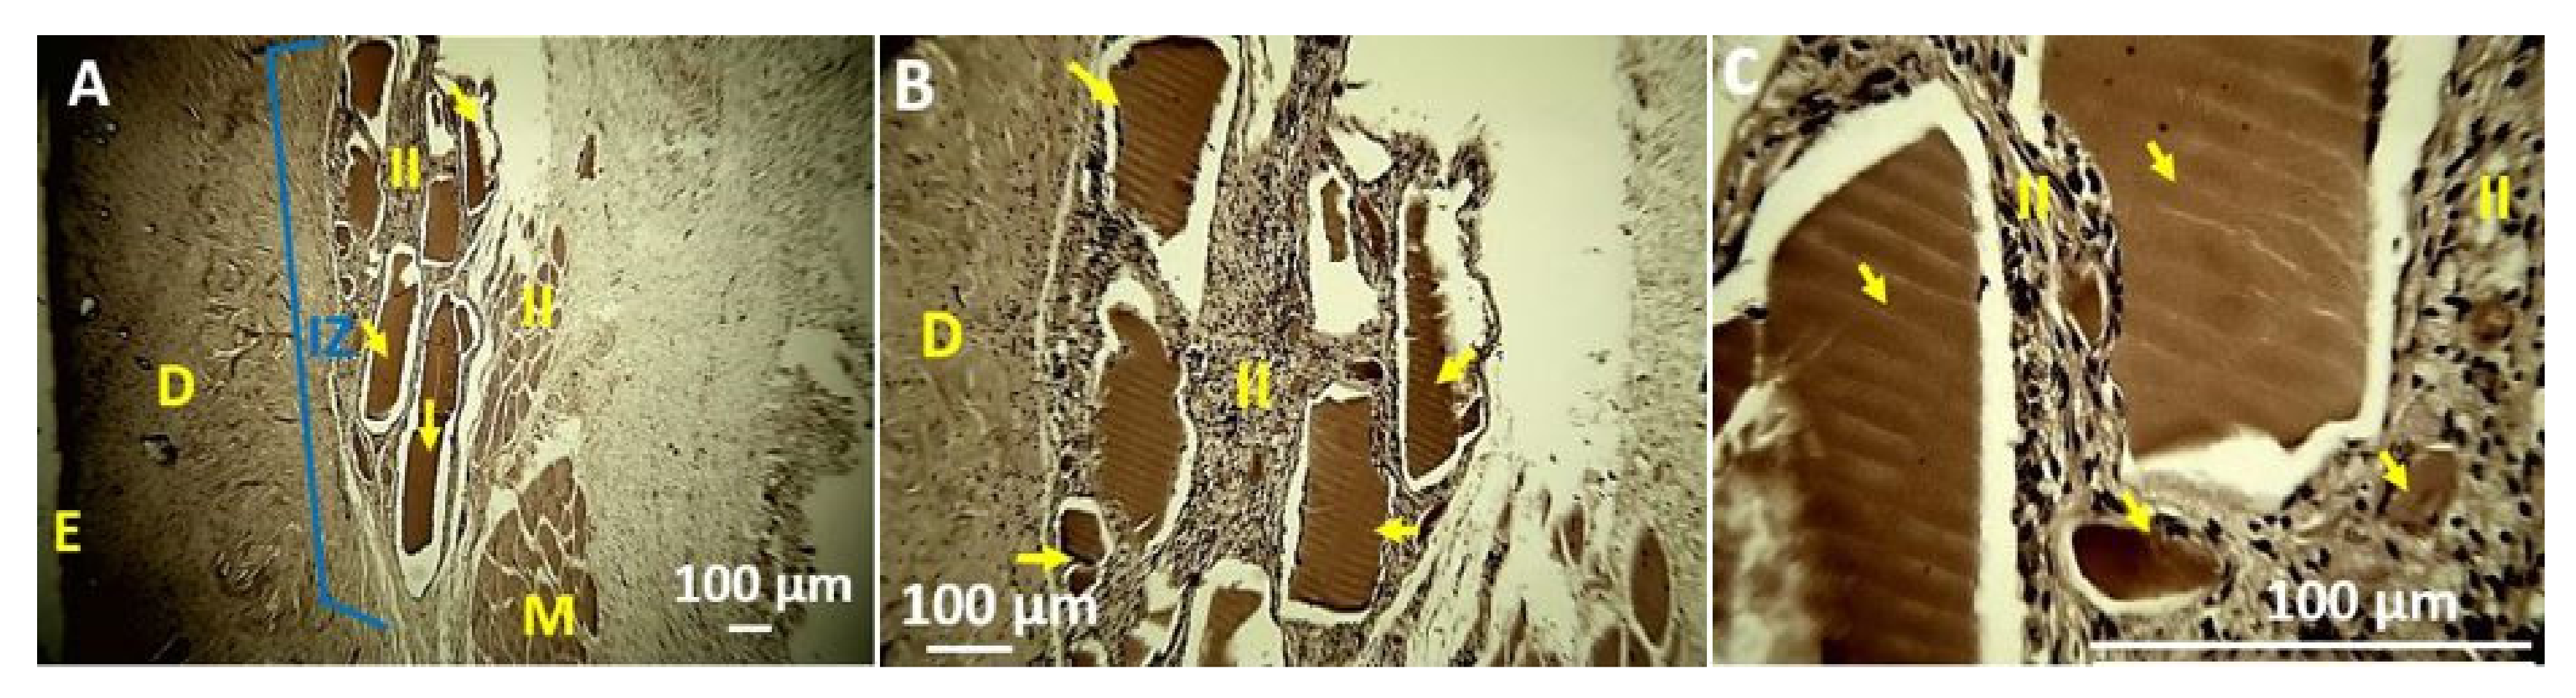

4. In Vivo Biocompatibility Tests of the CS/PVA/TTEO Films